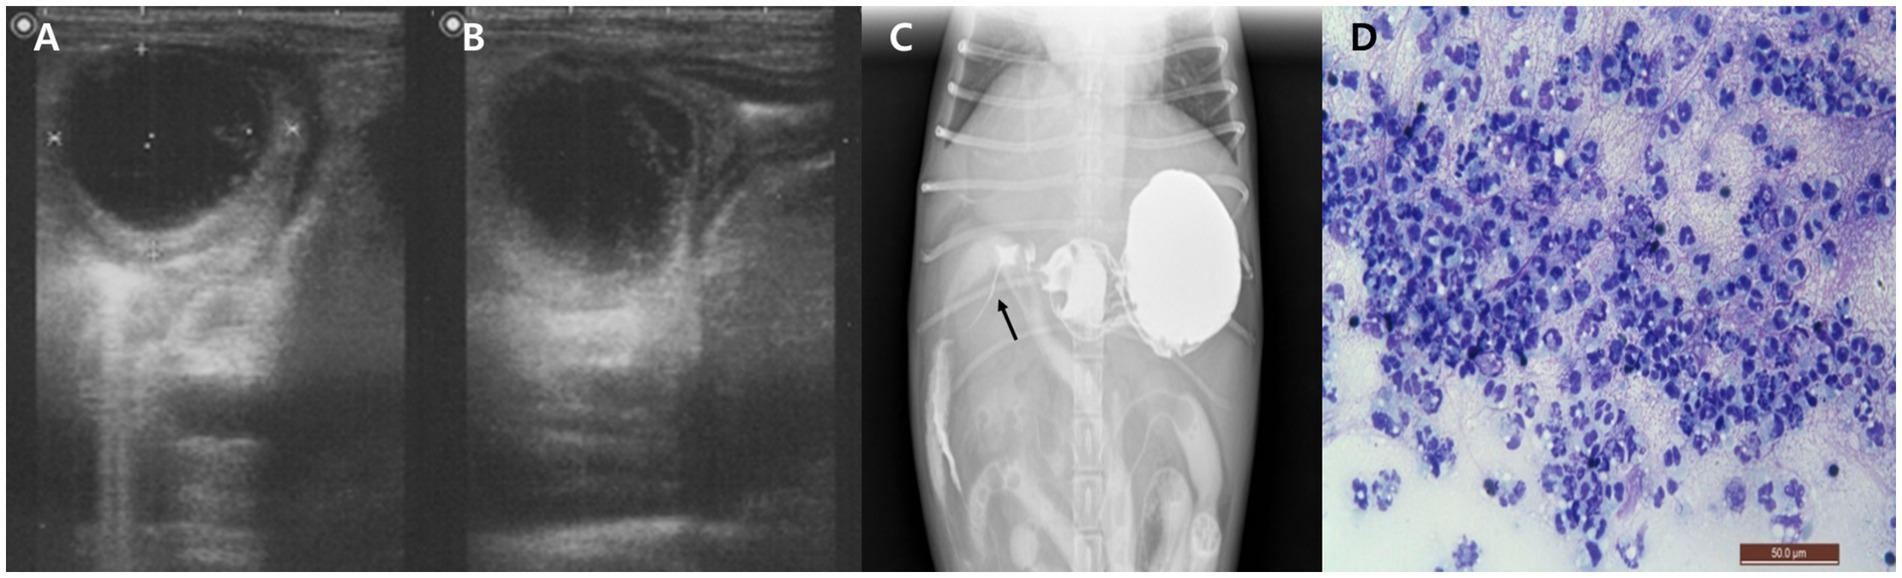

Right lateral and ventrodorsal abdominal radiographs showed increased soft tissue opacity in the right cranial abdomen and hepatomegaly. Ultrasonography identified a well-demarcated, hypoechoic, round mass (25.3 × 26.1 mm) within the cranial duodenal wall, accompanied by mild mural thickening (5.1 mm) and absence of detectable vascular flow on Doppler imaging (Figures 1A,B). The pancreas appeared diffusely hypoechoic and edematous. The gallbladder was mildly distended, and the common bile duct (CBD) was dilated, although its maximum diameter was not recorded. No abdominal effusion was identified on ultrasonographic examination. Despite these findings, the dog remained non-icteric on physical examination, and serum bilirubin levels were only mildly elevated, suggesting partial or early-stage biliary obstruction.

Figure 1. Imaging and cytological findings of an intramural duodenal abscess in a dog. (A,B) Abdominal ultrasonography showing a well-demarcated, round, hypoechoic mass (25.3 × 26.1 mm) within the cranial duodenal wall with mild mural thickening. (C) Positive contrast radiograph using oral barium sulfate demonstrates narrowed contrast passage with a thread-like appearance at the proximal duodenum (arrow). (D) Cytological smear of the duodenal lesion obtained via ultrasound-guided fine needle aspiration reveals abundant non-degenerate neutrophils without evidence of bacteria or neoplastic cells. Diff-Quik stain, 400×, scale bar = 50 μm.

After stabilization, to assess for potential duodenal luminal narrowing, a positive contrast study was performed using oral barium sulfate (30% w/w, 12 mL/kg; Solotop®, Taejoon Pharm, South Korea). Although oral contrast administration in vomiting patients carries inherent risks, the procedure was carried out cautiously and no complications occurred in this case. Radiographic and fluoroscopic images revealed narrowed contrast flow with a thread-like appearance at the proximal duodenum (Figure 1C). To further characterize the lesion, ultrasound-guided FNA of the duodenal mass was conducted. Cytological examination of the stained smear showed abundant non-degenerate neutrophils without evidence of bacteria or neoplastic cells (Figure 1D). Although frank purulent fluid was not aspirated, the cytologic findings supported an inflammatory process. The aspirated material was subjected to aerobic and anaerobic bacterial culture. All cultures yielded no growth, possibly reflecting prior antibiotic therapy or a sterile inflammatory lesion such as an aseptic abscess. Blood cultures performed at the time of presentation and repeated 24 h later were both negative.